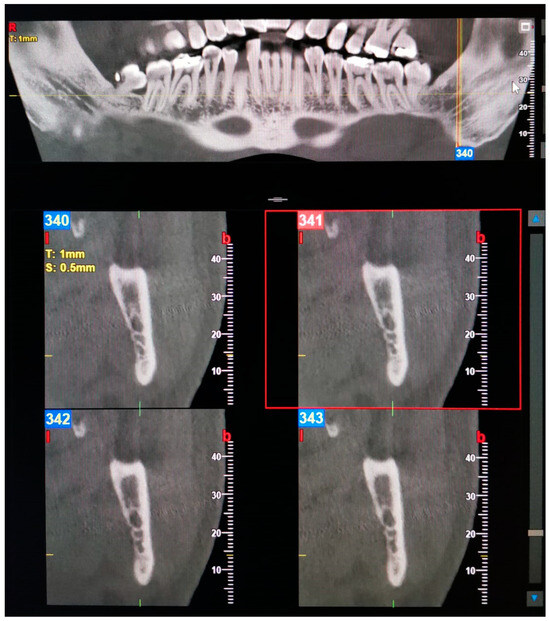

Figure 1. Panoramic view and transverse section of a bilateral Type 1—Retromolar (bifid mandibular canals) BMC. l, lingual. b, buccal. T, thickness. S, section.